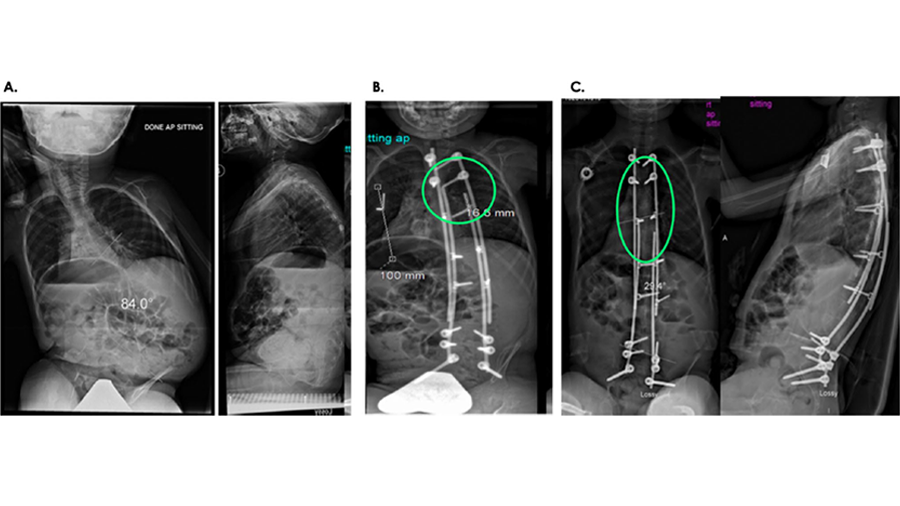

Fig 1: The TriALTIS™ Spine System